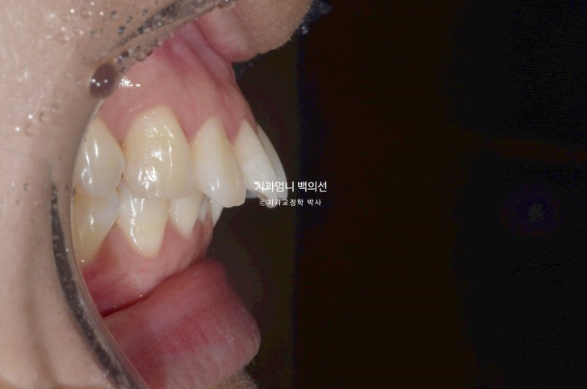

치료시작 8개월차 발치공간으로 앞니가 이동하면서 원래 깊었던 앞니 교합이 점점 더 깊어지는 것이 관찰됩니다.

이 부분 해결을 위해서는 원래 계획에 없었지만 앞니에 미니스크류 2개를 추가로 식립하고 고무줄을 걸기 시작합니다.

과개교합은 잘 개선이 되었습니다.

미니스크류와 고무줄의 조합은 인비절라인 발치교정이 성공으로 가는 노하우 입니다.

처음부터 계획하지는 않지만 적절하게 중간에 개입하여 부적절한 치아이동을 컨트롤 하는 중요한 도구입니다.

발치공간이 아직 남아있고 앞니 각도의 개선이 더 필요합니다.

아래 어금니들은 사랑니 공간으로 잘 이동했습니다.